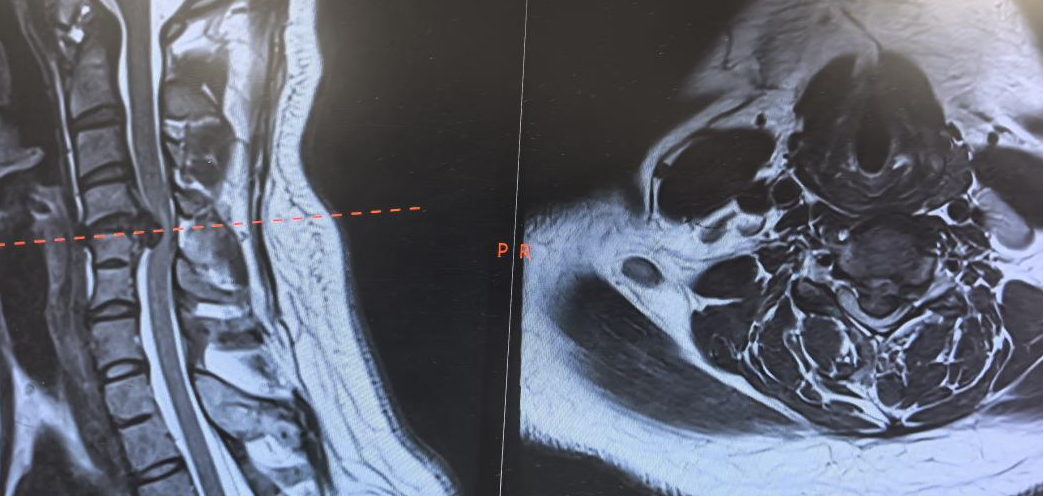

“不做手术,瘫痪是迟早的事;做手术,一半概率成功,一半概率直接瘫在手术台上。”当小王一家慕名找到西安市红会医院脊柱病院颈椎病区副主任医师王彪医生时,这样残酷的现实摆在了所有人面前。王彪结合病史及检查结果,颈椎间盘突出症诊断明确,且脱出髓核占到椎管的80%以上,属于巨大型椎间盘脱出,颈部脊髓严重受压。这是近几年临床比较少见的一例高风险颈椎手术,术中稍有不慎,就可能出现脊髓损伤导致瘫痪。巨大的风险让很多医院的医生望而却步。看着年轻姑娘眼中的绝望,想到她若失去行动能力的未来,医生的职责让王彪绝不推诿。术前谈话时,小王的父母紧紧攥着王彪医生的手,语气坚定:“医生,孩子就交给您了,我们相信您!”这份沉甸甸的信任,成了医护团队迎难而上的动力。